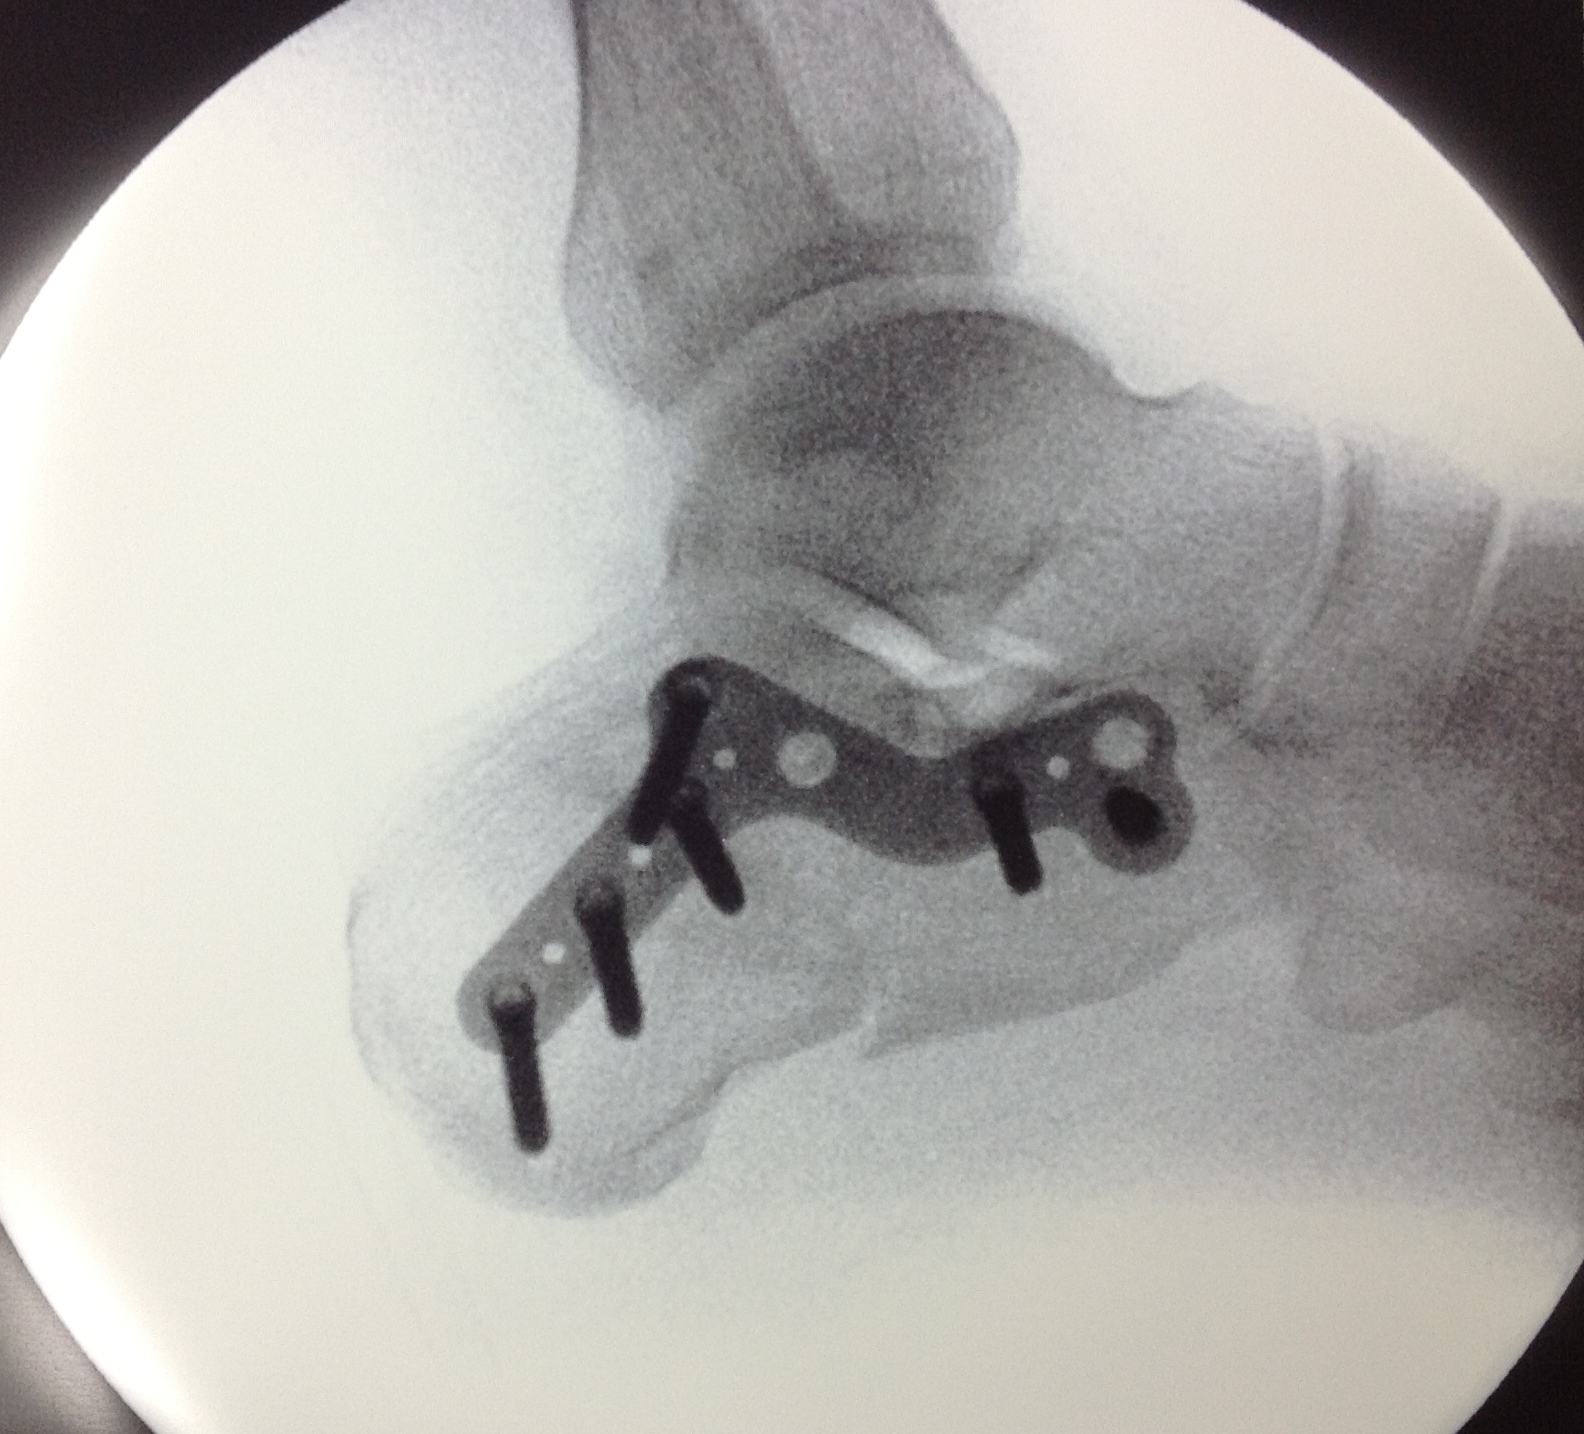

Fracturas de Calcáneo

Las fracturas de calcáneo (hueso del talón) son lesiones frecuentes por caídas de una altura o accidentes de tráfico.

La reconstrucción de estas fracturas es compleja y no exenta de complicaciones, por lo que es recomendable sean tratadas por cirujanos expertos. En nuestra Unidad tenemos amplia experiencia en el tratamiento de estas lesiones, tanto en la reconstrucción de las lesiones agudas como en la de las secuelas

Las radiografías y sobretodo el TAC ayudan a clarificar el tipo de fractura, el desplazamiento de los fragmentos óseos y el tratamiento a seguir.

El tratamiento intentará restablecer la anatomía, siendo para ello necesaria la intervención quirúrgica y la reconstrucción con placas específicas y tornillos.